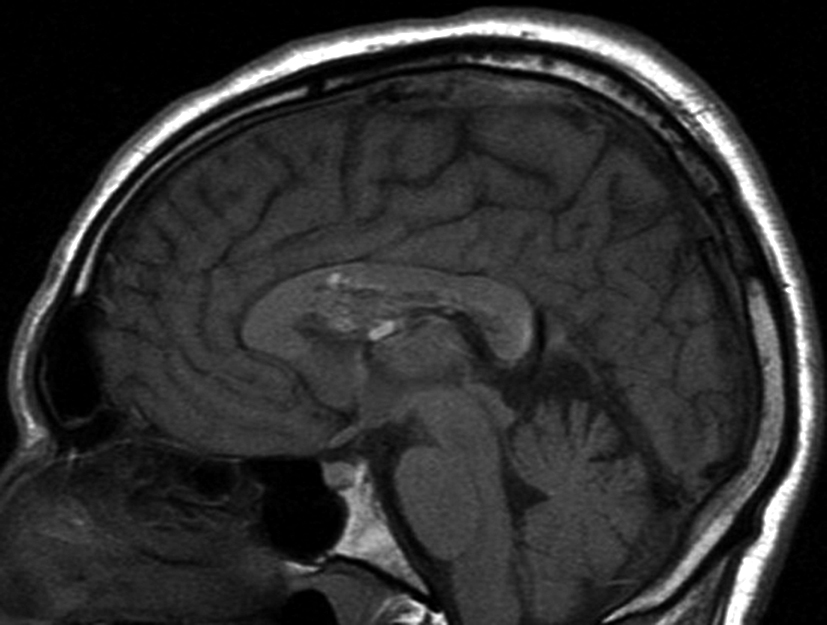

Con los hallazgos tomográficos, no se efectúan planteos diagnósticos y se realiza una resonancia magnética con la finalidad de obtener más datos semiológicos en busca de una aproximación diagnóstica. Se realizó el estudio por medio de secuencias T 1, FSE T 2, FLAIR, SWI y Difusión, en cortes axiales, FSE coronal y sagital T 1. Se realiza la administración de gadolinio DTPA en los tres planos. Se evidencia la lesión bien definida a nivel del ventrículo lateral derecho, que involucra al tronco del cuerpo calloso (Figura 2- C y 3- B). Presenta intensidad de señal heterogénea en secuencias T1 y T2 (Figura 3 y Figura 4). En secuencia ecogradiente se observa una señal marcadamente hipointensa y heterogénea, con un halo hipointenso bien definido (Figura 2- C). No presenta realce significativo tras la administración de Gadolinio (Figura 2- B) y en la secuencia de difusión no presenta restricción.

Figura 2 Resonancia magnética.

a) Imagen axial T1, lesión intraventricular con intensidad de señal heterogénea.

b) Tras la administración de Gadolinio no presenta realce significativo.

c) Imagen axial en secuencia ecogradiente donde se evidencia la lesión hipointensa y heterogénea. Se observa la extensión de la lesión al cuerpo calloso.

Figura 3

a y b) Imágenes sagitales T1, A. se observa la lesión a nivel del asta frontal de ventrículo lateral derecho y B. se evidencia la extensión al cuerpo calloso.